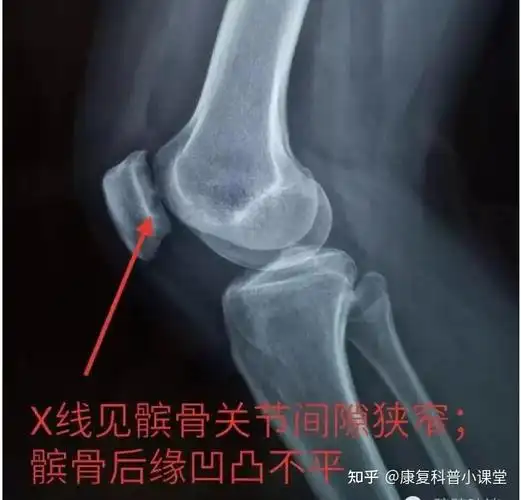

一例儿童髌骨脱位,讨论如何治疗 [病例帖]

髌骨骨折病人的x光片

征集髌骨骨折x光片按要求提供给予积分